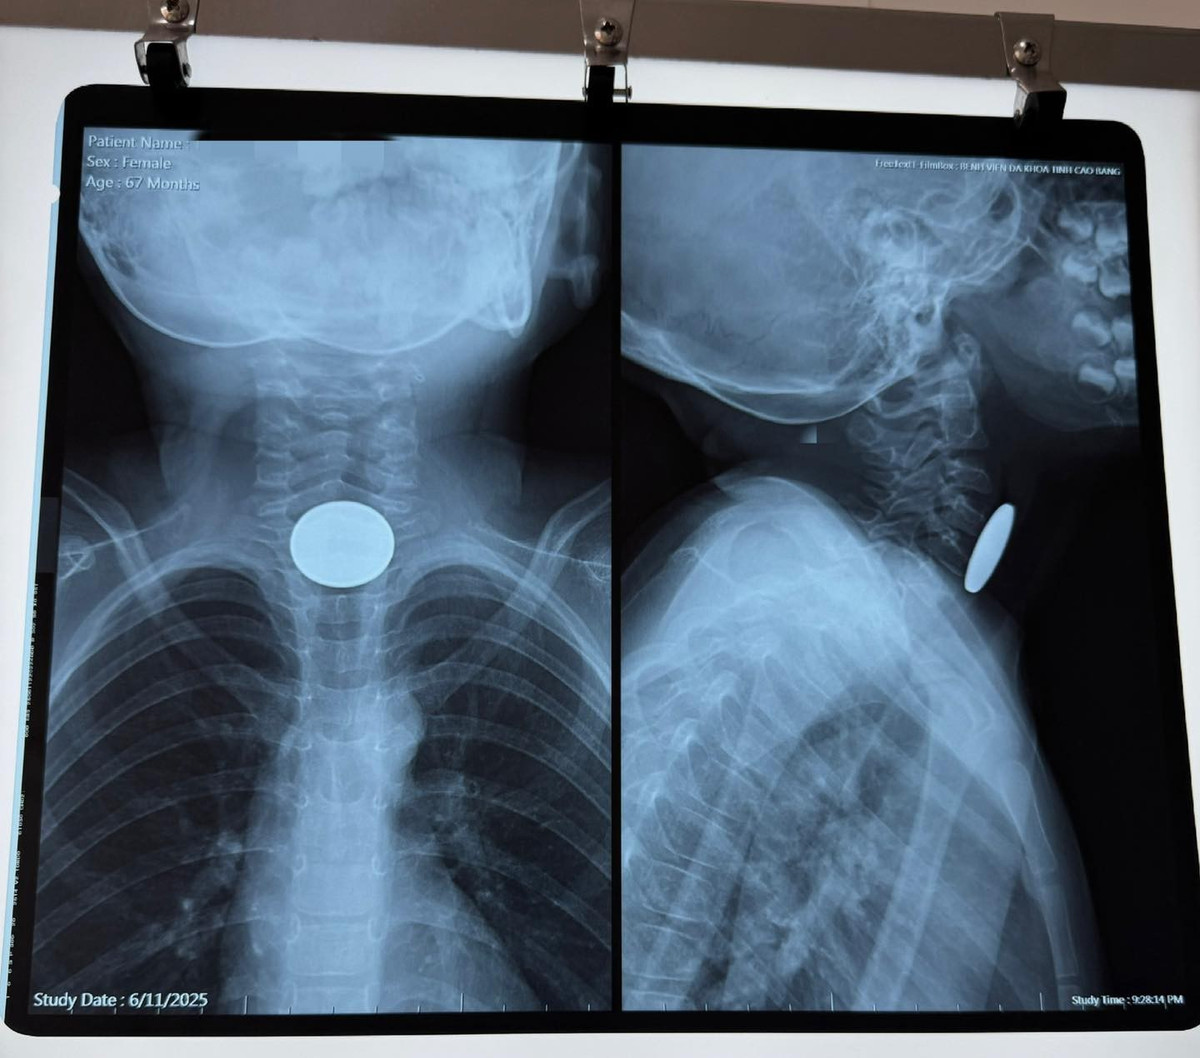

8. Bé gái nguy kịch vì nuốt đồng xu

Ngày 11/6, Bệnh viện Đa khoa tỉnh Cao Bằng tiếp nhận cấp cứu một bé gái 67 tháng tuổi trong tình trạng khó nuốt, buồn nôn, khó thở nghi do nuốt dị vật. Qua thăm khám, các bác sĩ xác định dị vật kim loại mắc trong thực quản và tiến hành nội soi khẩn cấp.

Dị vật được lấy ra là đồng xu kim loại đường kính 2,5cm, mắc cách cung răng trên 12cm. Bác sĩ Nông Hoàng Mạnh cho biết, nếu không xử trí kịp thời, bé có thể bị tắc thực quản, tổn thương niêm mạc hoặc nguy cơ tử vong nếu đồng xu lọt vào đường thở.

Ca nội soi thực hiện nhanh chóng, bé gái được theo dõi sát sao sau thủ thuật và hiện sức khỏe đã ổn định. Trường hợp này tiếp tục gióng lên hồi chuông cảnh báo về tai nạn dị vật ở trẻ nhỏ - nhóm có nguy cơ cao từ 6 tháng đến 6 tuổi.